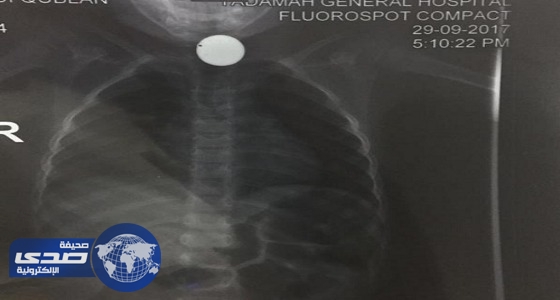

بالصور.. طفل يبتلع قطعة نقدية أثناء اللعب

فريق طبي ينقذ حياة طفل ابتلع قطعة معدنية في نجران